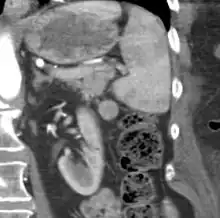

An accessory spleen is a small nodule of splenic tissue found apart from the main body of the spleen. Accessory spleens are found in approximately 10 percent of the population[1] and are typically around 1 centimetre in diameter. They may resemble a lymph node or a small spleen. They form either by the result of developmental anomalies or trauma.[2] They are medically significant in that they may result in interpretation errors in diagnostic imaging[2] or continued symptoms after therapeutic splenectomy.[1] Polysplenia is the presence of multiple accessory spleens rather than one normal spleen.

Accessory spleens may be formed during embryonic development when some of the cells from the developing spleen are deposited along the path from the midline, where the spleen forms, over to its final location on the left side of the abdomen by the 9th–11th ribs. The most common locations for accessory spleens are the hilum of the spleen and adjacent to the tail of the pancreas. They may be found anywhere along the splenic vessels, in the gastrosplenic ligament, the splenorenal ligament, the walls of the stomach or intestines,[3][4] the pancreatic tail,[5][6] the greater omentum,[7][8] the mesentery,[9] the renal fossa,[10][11] or the gonads and their path of descent.[12] The typical size is approximately 1 centimeter, but sizes ranging from a few millimeters up to 2–3 centimeters are not uncommon.[2]

If splenectomy is performed for conditions in which blood cells are sequestered in the spleen, failure to remove accessory spleens may result in the failure of the condition to resolve.[1] During medical imaging, accessory spleens may be confused for enlarged lymph nodes or neoplastic growth in the tail of the pancreas,[5] gastrointestinal tract, adrenal glands or gonads.[2]